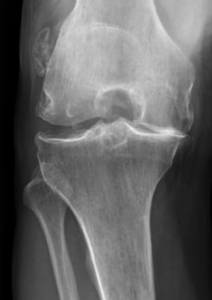

Le diagnostic repose sur un faisceau d’arguments cliniques (interrogatoire, examen physique) et sur l’imagerie (pincement de l’articulation, présence d’ostéophytes ou « becs » osseux). Lorsque ces signes sont présents, il n’est pas nécessaire d’effectuer d’autres examens à visée diagnostique que la radiographie standard.

Lorsque l’usure du genou atteint 2 ou 3 compartiments (gonarthrose tricompartimentale) (Fig.7)

a échoué, la seule solution chirurgicale est la prothèse totale du genou. Elle consiste à remplacer les 2 compartiments fémorotibiaux (interne et externe), avec ou sans remplacement de la rotule (resurfaçage).

L’objectif de cette intervention est de retrouver un genou indolore, stable, et mobile. La prothèse totale permet de corriger une déviation du genou, contrairement à la prothèse unicompartimentale.